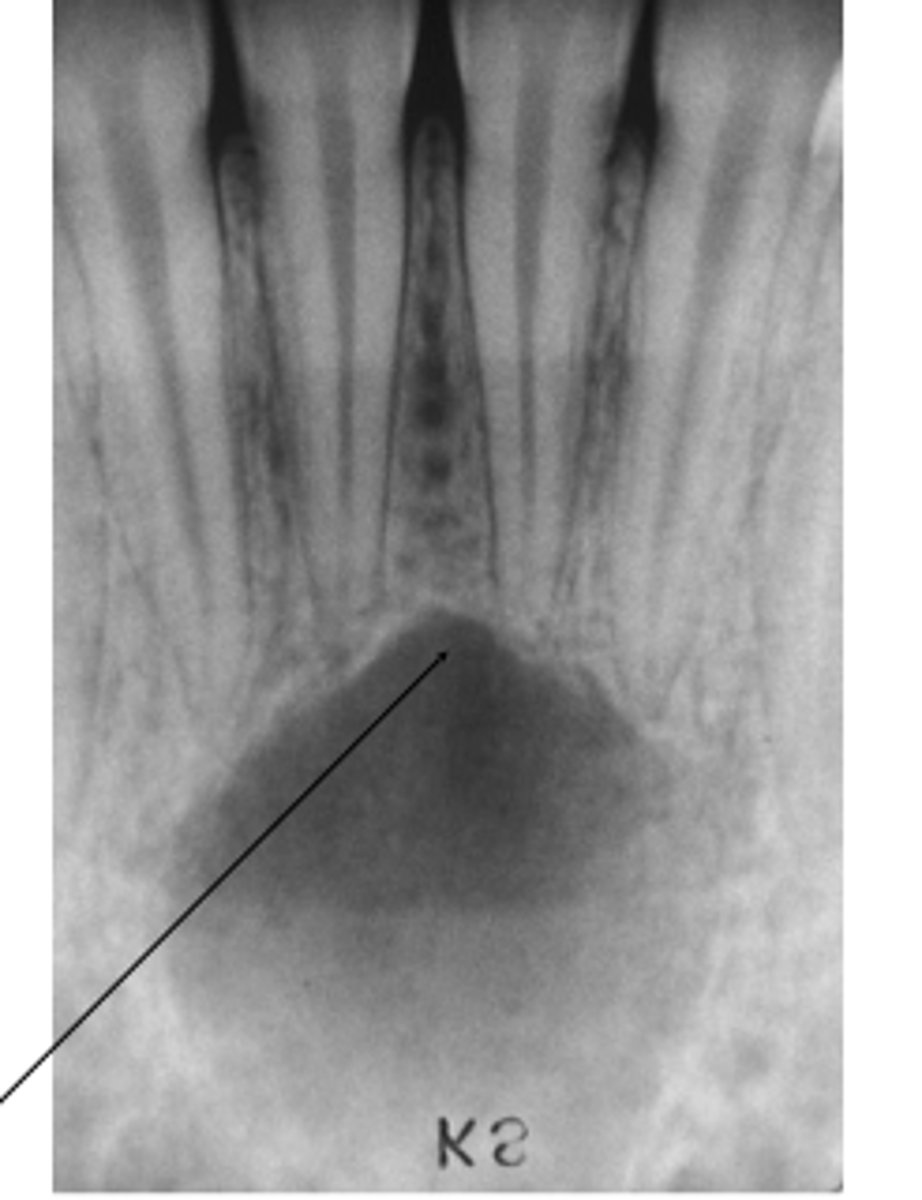

Empty or fluid-containing bone cavity

Pseudocyst (lacks epithelial lining)

Where does simple bone cysts typically occour?

Marked mandibular predominance

What is a clinical manifestation associated with simple bone cysts?

20% of patients present painless jaw swelling

Jaw lesions are normally asymptomatic.

diagnosed by radiographic examination.

what is the diagnosis for simple bone cyst?

Radiographic signs are not specific

• Surgical exploration is required